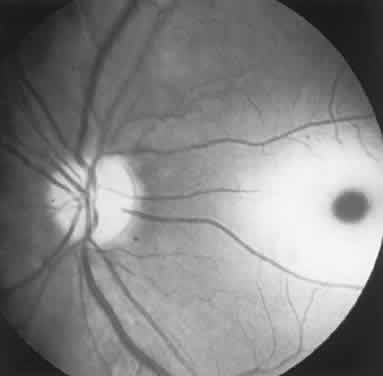

The retinal variety may be admixed in a person who suffers the more conventional attacks of migraine. It is presumed that vasospasm in the retinal circulation determines transient hypoxia, perhaps somewhat similar to the visual cortical event. On rare occasions, the fundus has been examined during typical retinal migraine episodes, and arterial constriction has been described. Wolter and Burchfield106 photographically documented such an episode and demonstrated mild “retinal edema”; vessel narrowing is also evident (Fig. 8). Fortunately, permanent complications of retinal migraine are rare. These may take the form of central retinal artery occlusion or ischemic papillopathy (see Volume 2, Chapter 16); nerve fiber bundle visual field defects may be demonstrated (Fig. 9).

Fig. 8. Retinal migraine. A. During amaurotic episode. Note the dusky appearance of the fundus, increased retinal sheen (possibly edema), and dark narrowed veins (arrows). The disc is also hyperemic. B. Fundus after episode. Compare paired arrows. (Courtesy of Dr. J. Reimer Wolter)

Fig. 9. An 18-year-old student with recurrent episodes of left retinal migraine. After a typical attack, he noted an inferior field defect. A. Fundus shows a defect in the superior arcuate nerve fiber bundle (between arrows: compare fiber layer below disc). B. Visual field defect corresponds to a retinal nerve fiber layer defect.